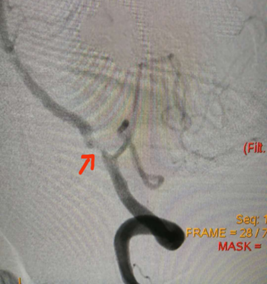

术前检查,左侧椎动脉V4段重度狭窄

患者病情平稳,但隐患并未排除,有可能再次发生脑卒中,就像绑了个“定时炸弹”,随时危及生命。鉴于此,神经医学中心进一步对周先生血管功能和侧枝循环进行评估,确定其有血管内治疗的充分指征。7月17日神经医学中心刁士元副主任医师对周先生进行全脑血管造影,评估了血管径路并再次确认了患者血流代偿的状况。经过充分的术前讨论和周密准备,7月26日,中山七院神经医学团队为其开展左侧椎动脉颅内段支架置入术。术后即刻造影显示,左侧椎动脉颅内段狭窄解除,术前显影不良的左侧大脑后动脉完全显影;复查头颅CT未出现脑出血及造影剂渗漏;复查脑多普勒超声,左侧椎动脉血流恢复正常。这意味着,原先重度狭窄的左侧椎动脉颅内段得到扩张,血流恢复正常,手术取得满意的治疗效果。

支架置入术后复查,血流恢复正常